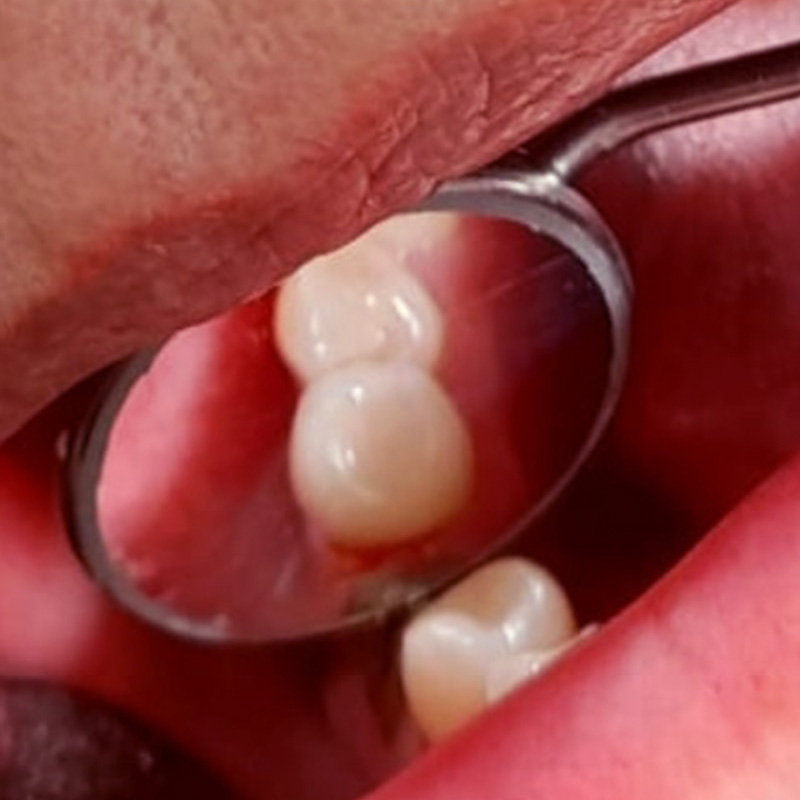

До и после лечения

После осмотра и предварительной диагностики врач Мельников Алексей Владимирович рекомендовал провести имплантацию с последующим протезированием металлокерамическими конструкциями. После согласования плана лечения с пациентом приступили к лечению.

- установка 3 имплантов системы Alpha Bio;

- изготовление и установка металлокерамических коронок на имлантах системы Alpha Bio.